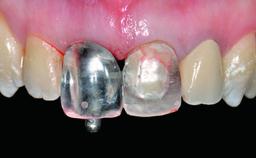

A healthy 28-year-old female patient presented for a consultation on treatment options to restore her upper right central incisor. At the clinical examination, the tooth responded to percussion and palpation. The gingiva was red and slightly swollen, with a mid-facial probing depth of 10 mm. The upper right lateral incisor showed no signs or symptoms, did not respond to exploration and percussion, and the vitality test was positive. The periapical radiograph revealed that tooth 11 had been endodontically treated, with no lesion evident at the apex. A small radiopaque calcified structure surrounded by a narrow radiolucent zone (3 × 3 mm) was present at the apex of tooth 12.

Retention Screw-retained Screw-retained

Provisional Implant-Supported Prosthesis Prosthodontic margin > 3 mm apical to mucosal margin Prosthodontic margin > 3 mm apical to mucosal margin